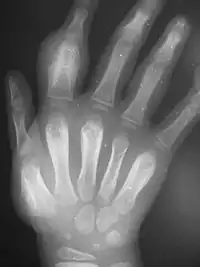

Secondary yaws affects the skin and bones.[13] The most common bone-related problem is periostitis, an inflammation around the bone, often occurs in the bones of the fingers and the long bones of the lower arms and legs, causing swollen fingers and limbs.[13] This causes pain at night and thickening of the affected bones (periostitis).[2] About 75% of infected children surveyed in Papua New Guinea reported joint pain.[2] Swollen lymph nodes, fever, and malaise are also common.[13]

Tertiary yaws can include gummatous nodules. It most commonly affects the skin. The skin of the palms and soles may thicken (hyperkeratosis). Nodules ulcerating near joints can cause tissue death. Periostitis can be much more severe. The shinbones may become bowed (saber shin)[13] from chronic periostitis.[2]